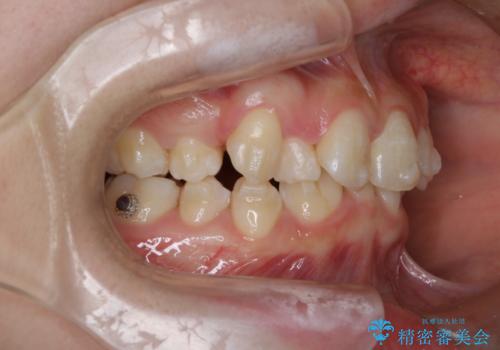

- 20代女性

- 1年9ヶ月

- 前歯のガタガタを主訴に来院されました。

抜歯を行い、インビザラインにて治療を完了しております。